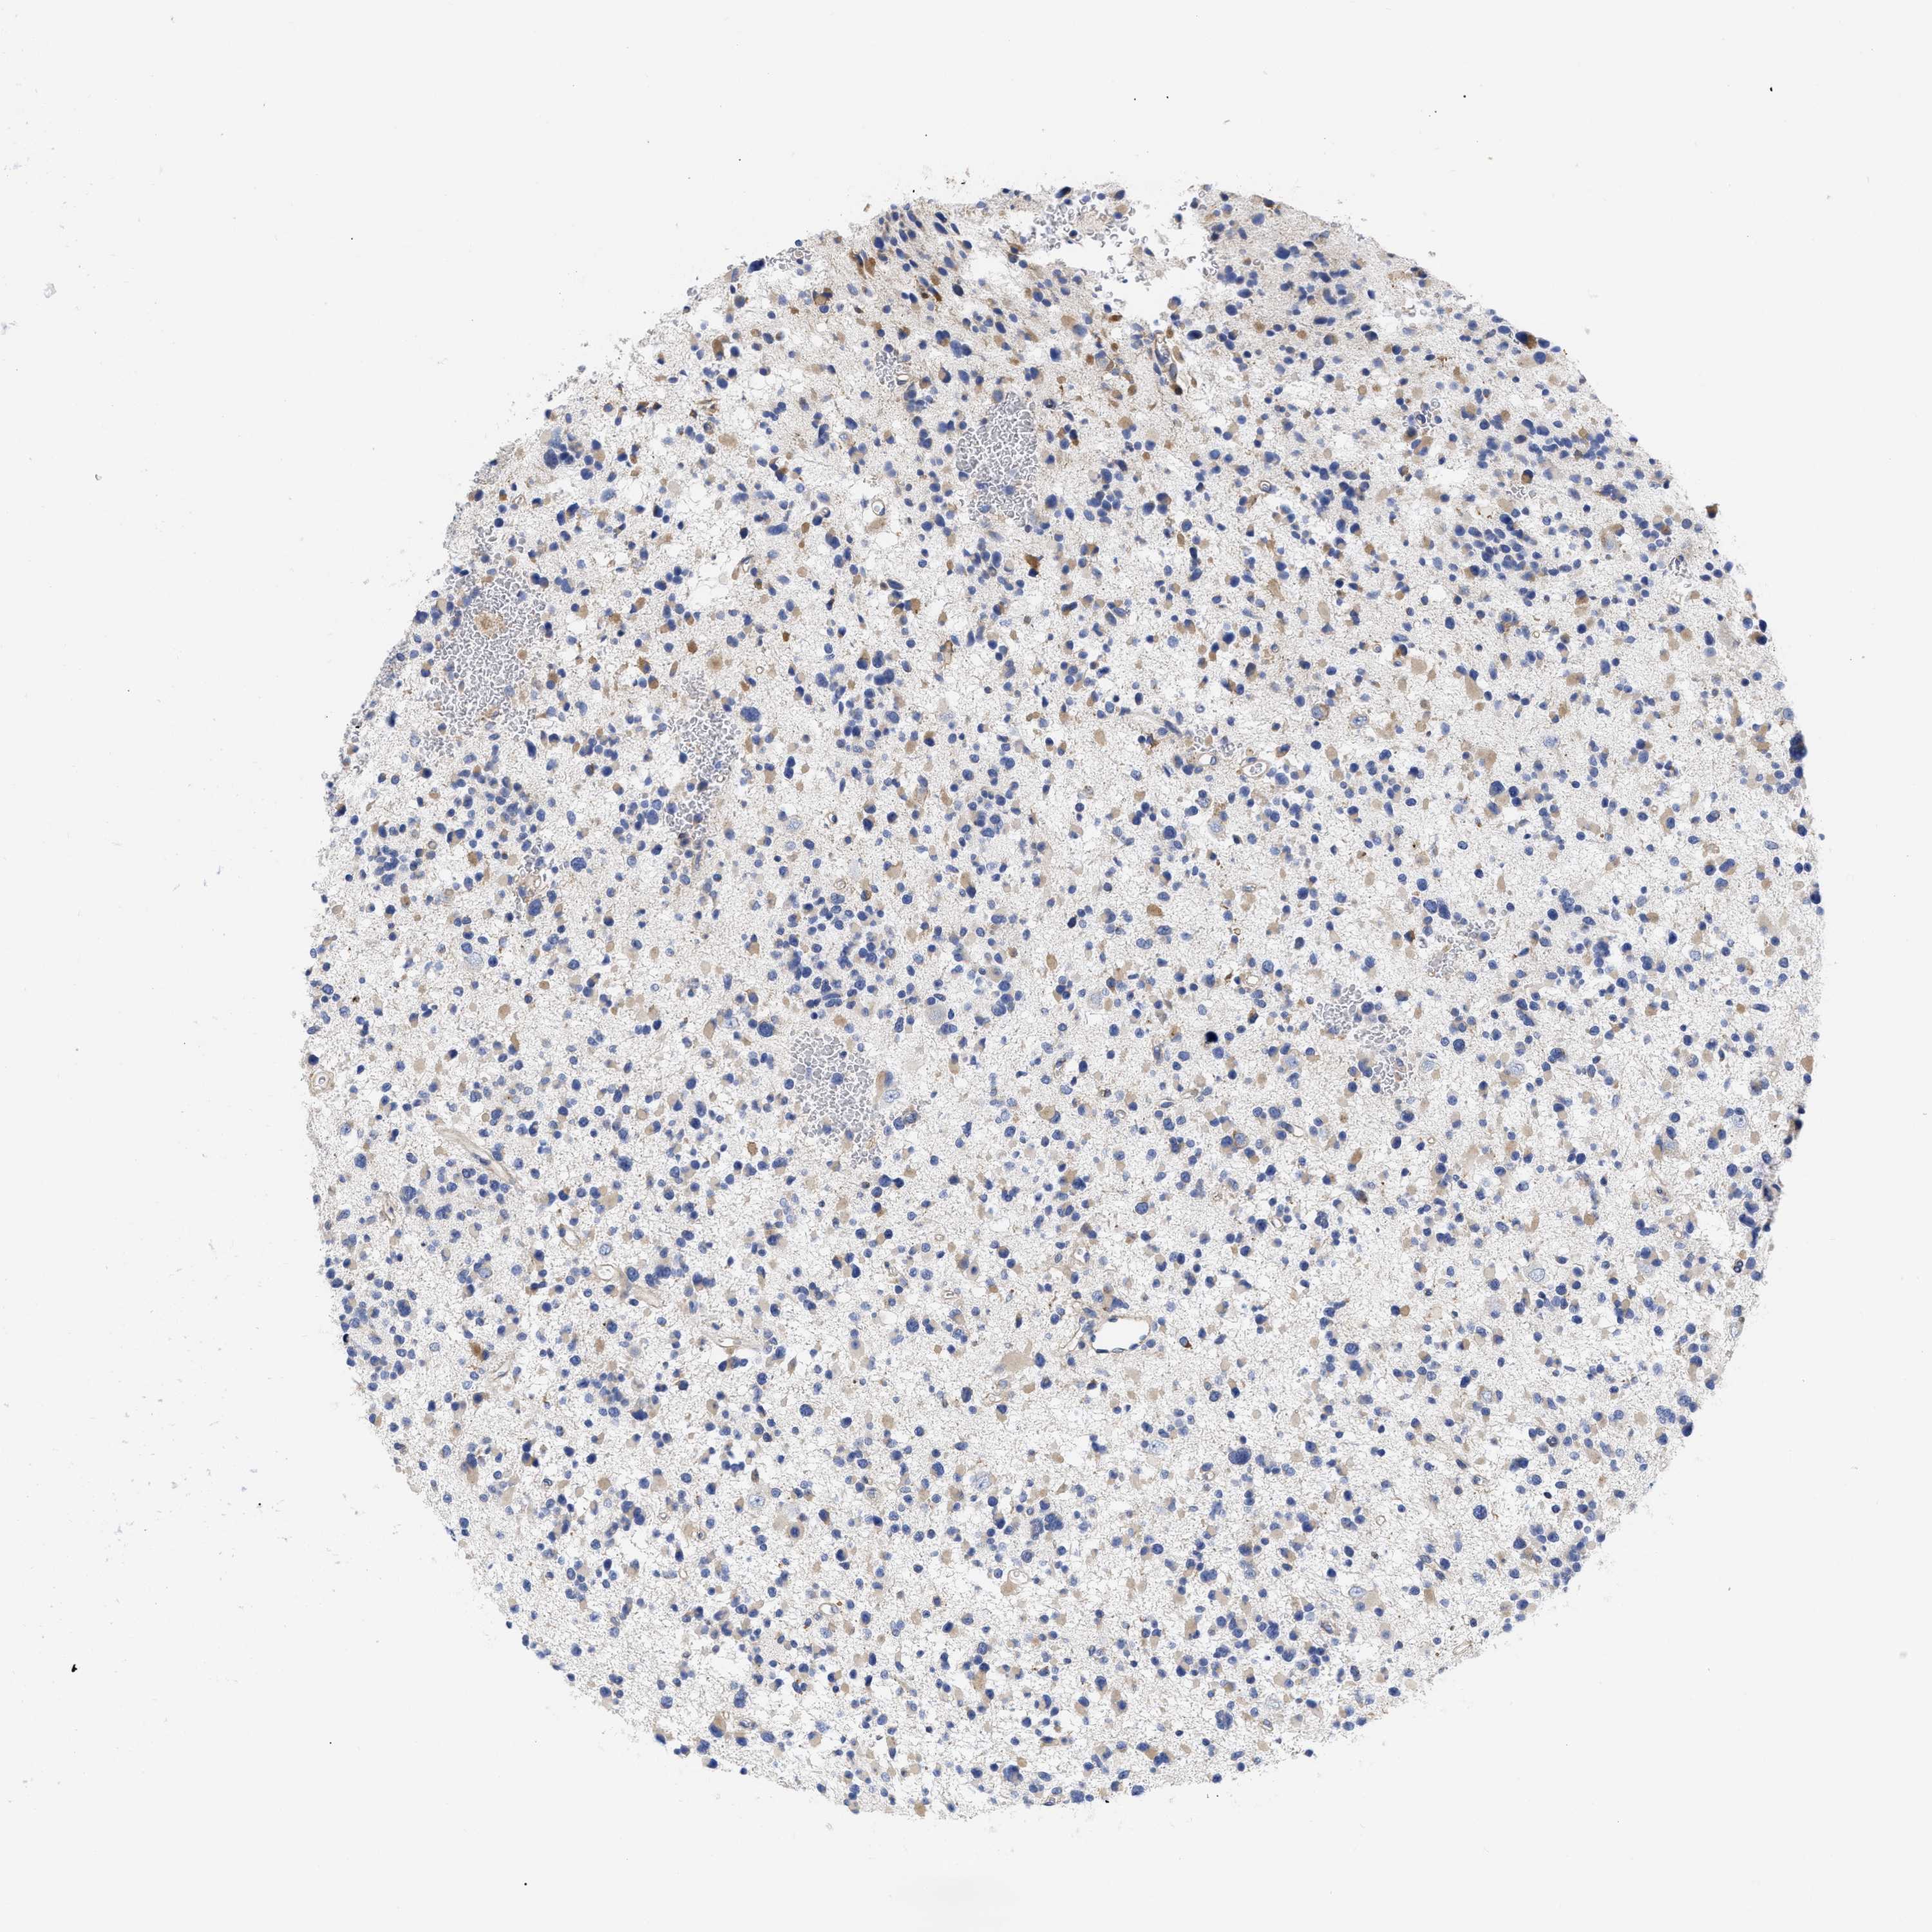

GLIOMA - Protein expressioni

A mouse-over function shows sample information and annotation data. Click on an image to view it in a full screen mode. Samples can be filtered based on level of antibody staining by selecting one or several of the following categories: high, medium, low and not detected. The assay and annotation is described here.

Note that samples used for immunohistochemistry by the Human Protein Atlas do not correspond to samples in the TCGA dataset.

Antibody stainingi

Antibody staining in the annotated cell types in the current human tissue is reported as not detected, low, medium, or high, based on conventional immunohistochemistry profiling in selected tissues. This score is based on the combination of the staining intensity and fraction of stained cells.

Each image is clickable and will lead to virtual microscopy that enables deeper exploration of all samples and also displays staining intensity scores, fraction scores and subcellular localization as well as patient and tissue information for each sample.

Antibody HPA018453

Antibody HPA019055

Antibody HPA028849

Antibody CAB034170

Glioma, malignant, High grade

Glioma, malignant, Low grade

Glioblastoma, NOS